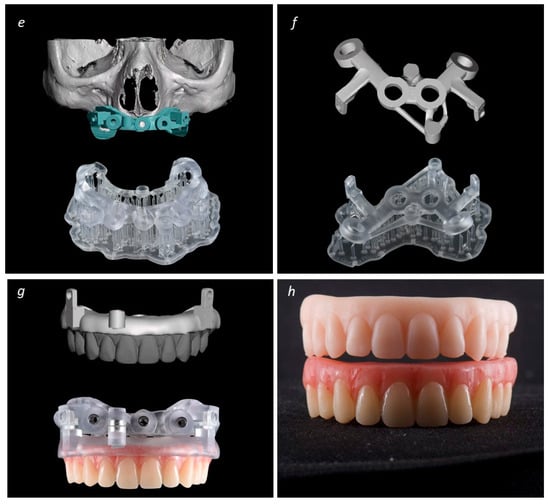

Description of the Technique